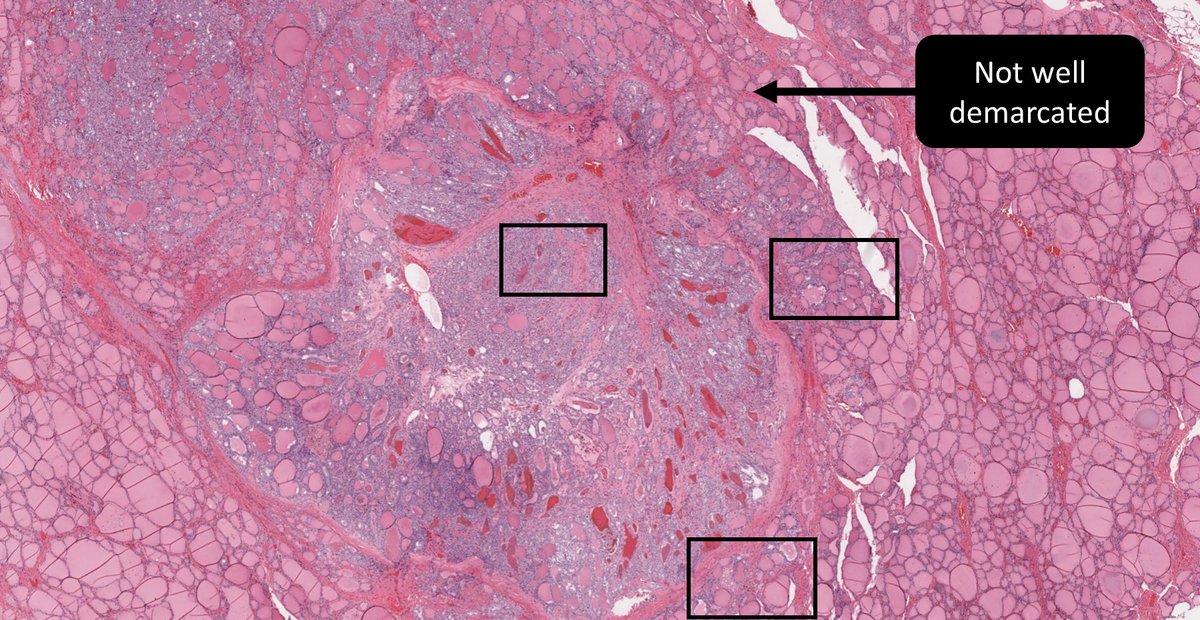

____ Follicular Variant Papillary Thyroid Carcinoma A) Non-invasive encapsulated B) Invasive encapsulated C) Invasive D) None of the above 🔬dpa-dapa.com/public/display… #EndoPath #ENTPath #PathTwitter #PathResidents

DrCycloPath's tweet image. ____ Follicular Variant Papillary Thyroid Carcinoma

A) Non-invasive encapsulated

B) Invasive encapsulated

C) Invasive

D) None of the above

🔬dpa-dapa.com/public/display…

#EndoPath #ENTPath #PathTwitter #PathResidents